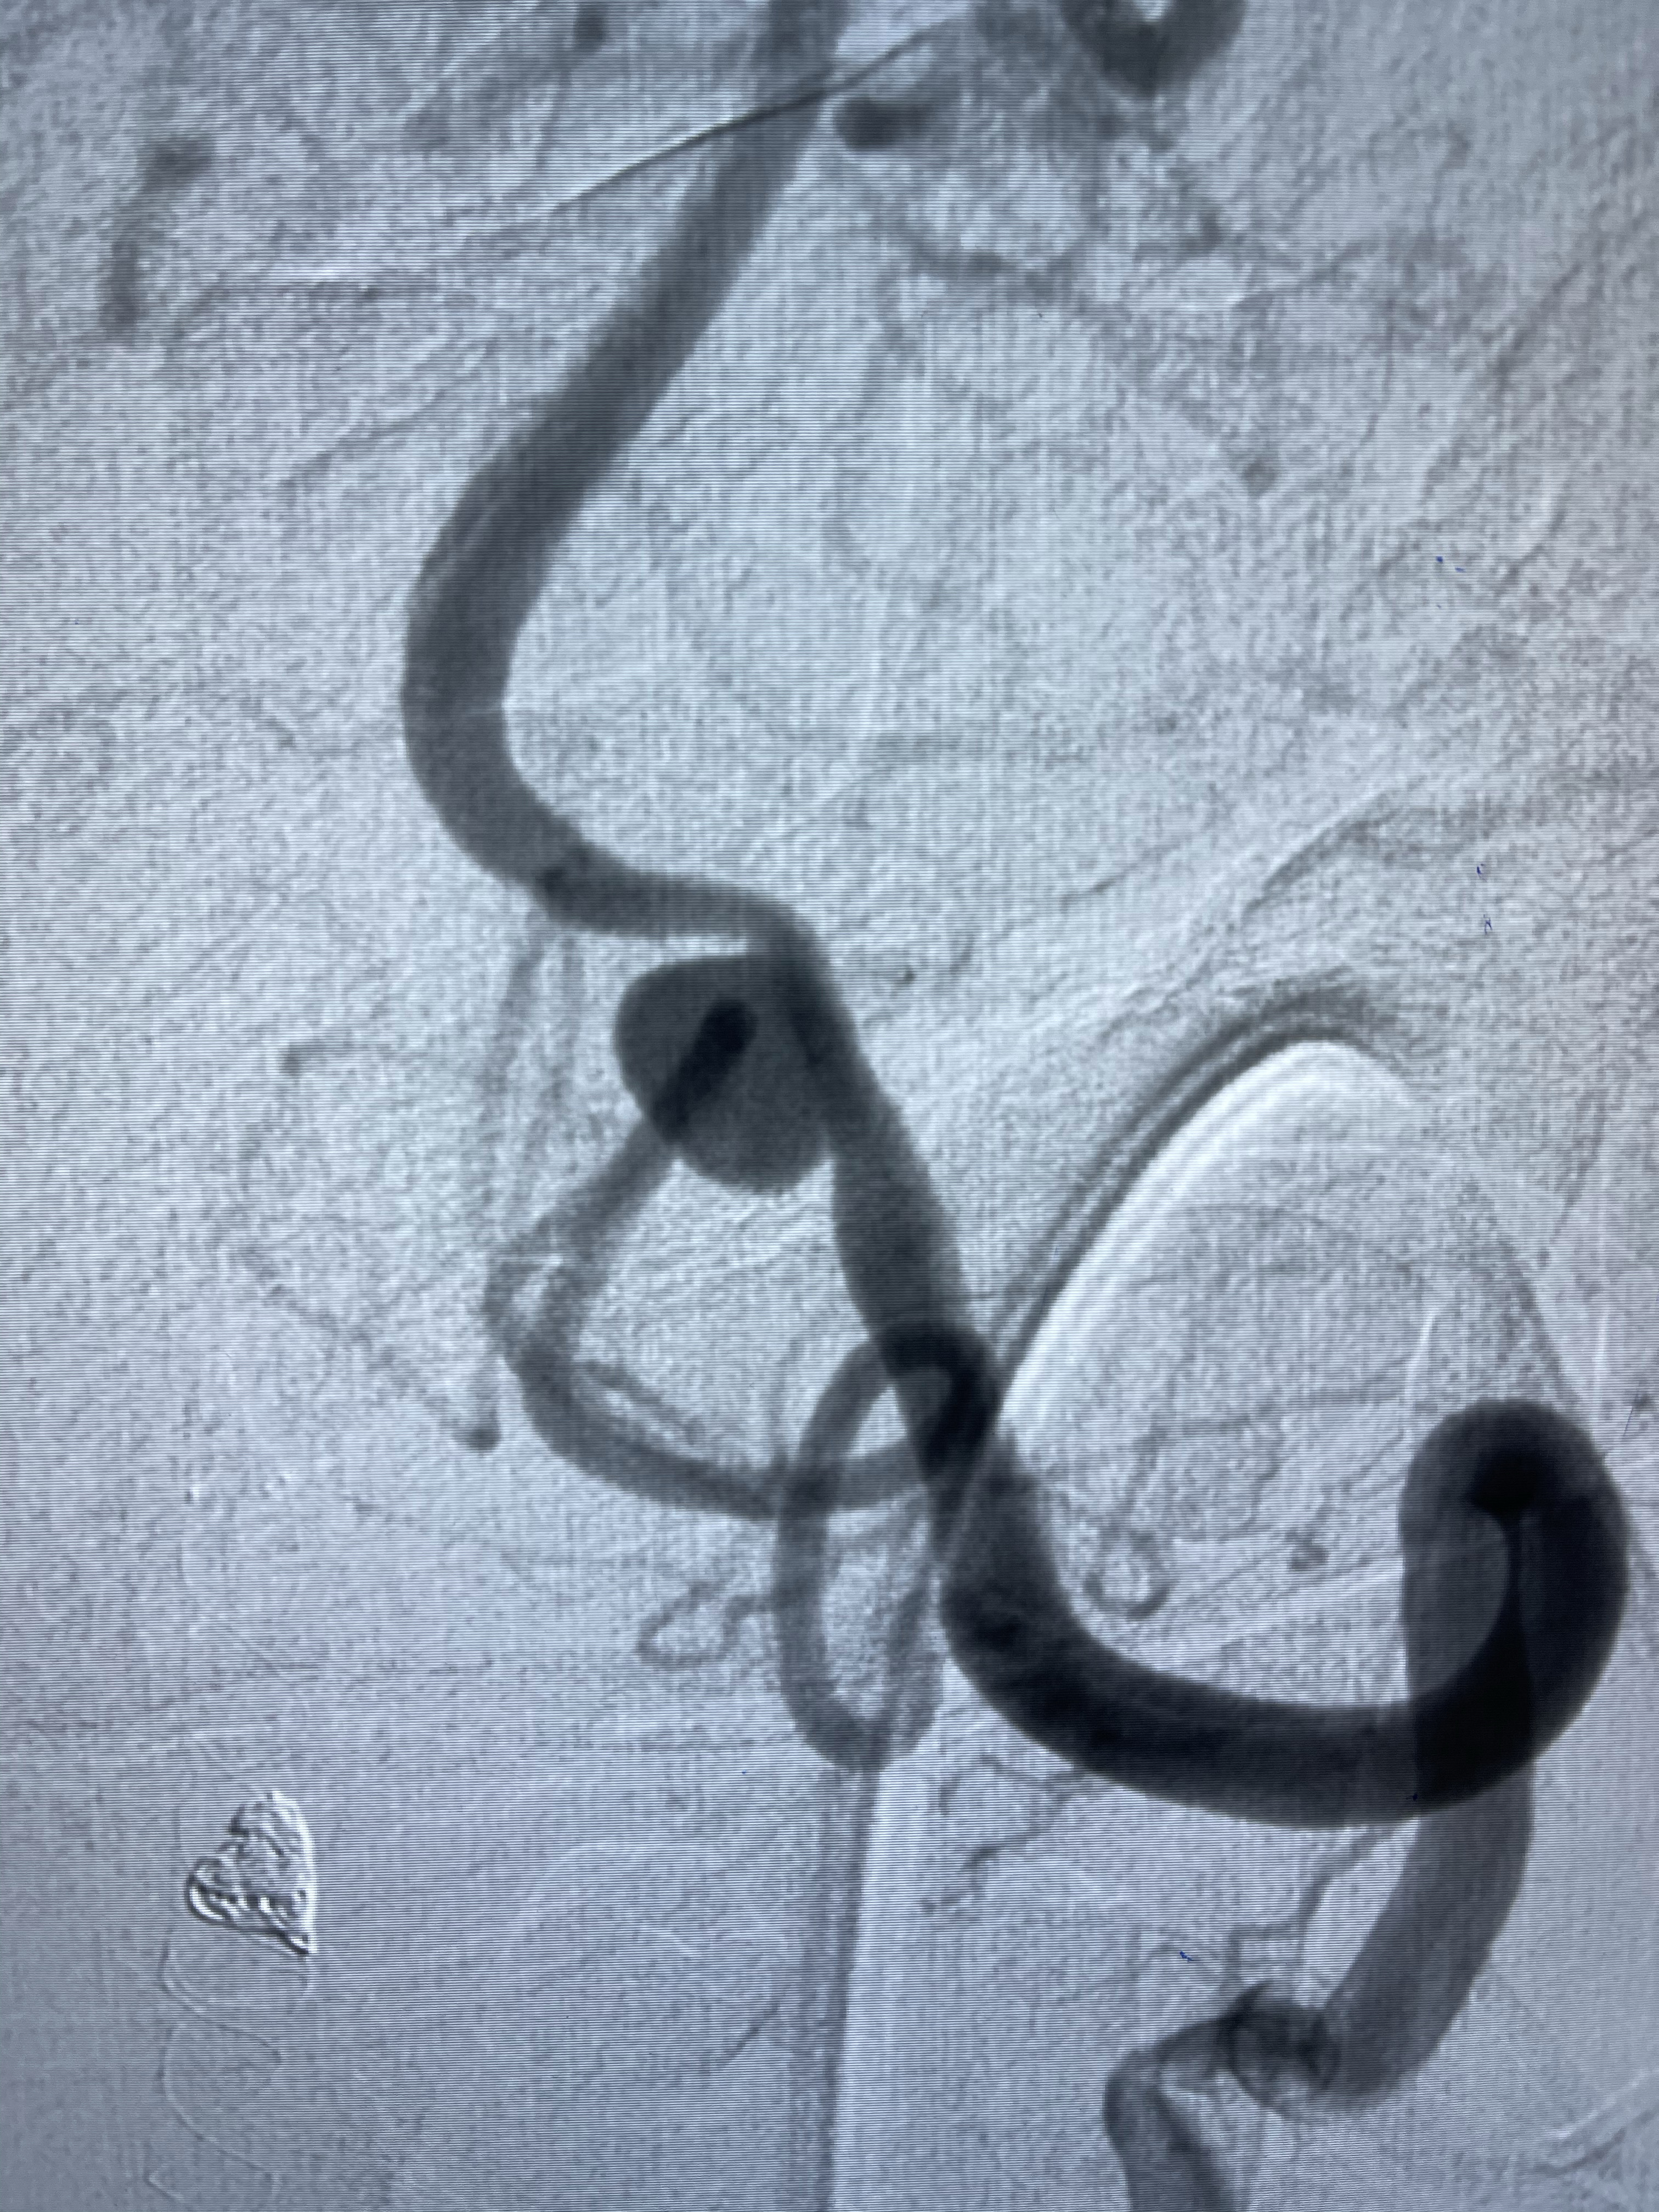

右侧颈内动脉夹层动脉瘤Lvis5.5-20mm支架辅助栓塞

左侧椎动脉V4夹层动脉瘤多支架辅助栓塞:

1.Enterprise4.0-23mm;

2.Tubridge3.5-30mm密网支架

即刻造影